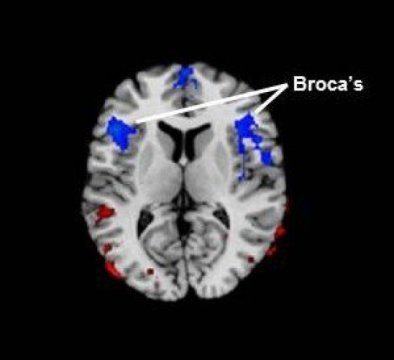

Dem klassischen Modell zufolge werden die Aphasien in Abhängigkeit des Ortes der zugrunde liegenden zerebralen Läsion klassifiziert. Mit diesem Modell als Grundlage, ist die Broca-Aphasie demnach die Konsequenz einer Läsion im Broca-Areal. Das Broca-Areal befindet sich auf der Großhirnrinde und ist meist im linken Frontrallappen angesiedelt. Das Broca-Areal ist für verschiedene Sprachkomponenten verantwortlich: die Anordnung der Phoneme (Laute) in Wörtern, die Organisation der Wörter im Satz (Syntax), die semantische Integration und die motorische Planung der Sprache.